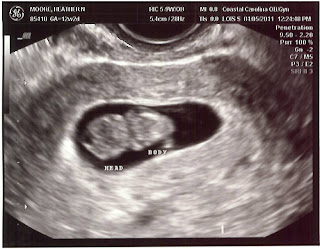

I went to the doctor last Tuesday to get an ultrasound done since I was absolutely sure I wasn't eleven weeks pregnant when I went to the doctor the week before. Turns out I was right. The ultrasound of little birdie showed a strong heartbeat of 160 bpm and the forming of a head and body. We got to see he/she move a little while doing the u/s. It is so weird to see something moving around inside of you when you can't feel it.

So it turns out that I was 8 weeks 6 days pregnant when I went on Tuesday. That makes my new due date November 9, 2011. So here is our little birds first picture!